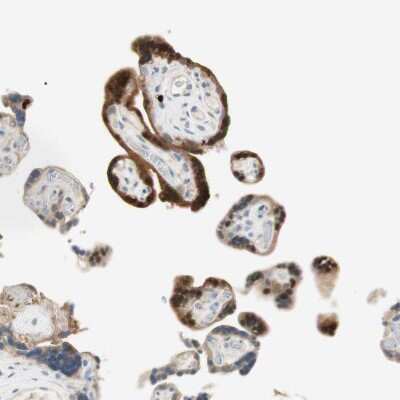

Immunohistochemistry-Paraffin: 15-PGDH/HPGD Antibody [NBP1-87062] - Staining of human placenta shows moderate to strong cytoplasmic positivity in trophoblastic cells.